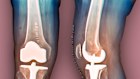

An X-ray of a 69-year-old’s knees after a total knee replacement. Exercise could help you avoid one.

3 science-backed ways to avoid a knee replacement

Inactivity is not an effective solution to knee pain – it could worsen it. Here are three expert rules to bulletproof your joints.